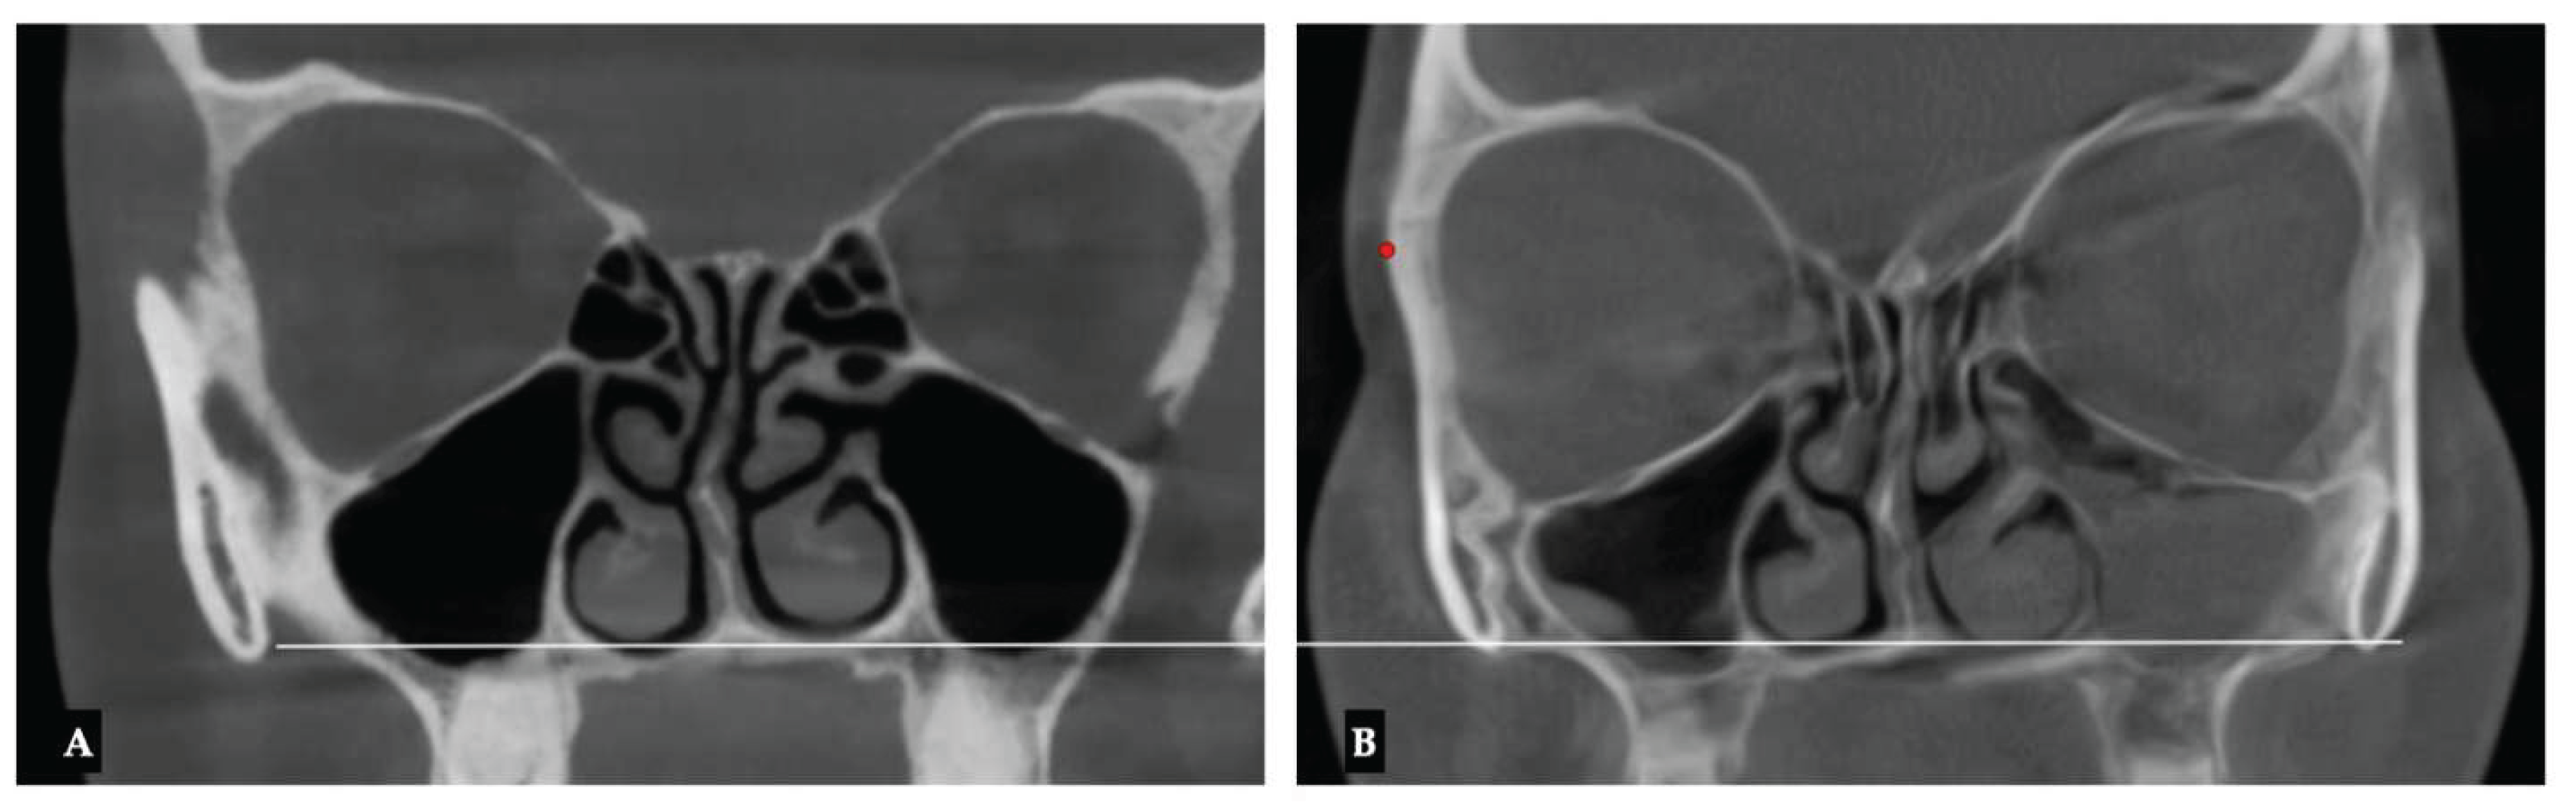

Background: While mini-screw-assisted rapid palatal expansion (MARPE) is effective for correcting maxillary transverse deficiency in adults, perimaxillary suture disarticulation—particularly at the pterygomaxillary junction—can be inconsistent. This study evaluates skeletal and dentoalveolar outcomes of a novel 3D-guided midpalatal piezocorticotomy-assisted MARPE protocol, focusing on expansion symmetry and pre-existing asymmetries. Methods: Three adult patients were retrospectively analyzed after treatment with 3D-guided midpalatal piezocorticotomy-assisted MARPE expansion and one with non-guided midpapalatal piezocorticotomy and MARPE expansion. Surgical guides were digitally designed using CBCT data to align with the nasal septum orientation in multiple planes. Perimaxillary suture disarticulation was measured pre- and post-expansion, and dentoalveolar changes were evaluated. Post-expansion asymmetries were addressed using directly printed aligners. Results: Complete midpalatal suture separation (mean 8.48 mm), involving both anterior and posterior nasal spine regions, was achieved in one patient. Bilateral pterygomaxillary disarticulation averaged 1.06–1.23 mm, resulting in forward–outward rotation of the nasomaxillary complex. Additional separation occurred at the frontonasal (2.03 mm) and vomeromaxillary (1–2 mm) sutures, with no significant changes in orbital or peri-orbital sutures. One patient presented with pre-existing dentoalveolar asymmetry, which intensified the perceived post-expansion imbalance but was successfully corrected with directly printed aligners. In the second case, 5.6 mm of suture separation resulted in a limited lateral nasal width increase (<1.5 mm), while maxillary base expansion exceeded 6 mm. A significant canine plane cant (1.2 mm) and divergent axial inclinations of the maxillary central incisors relative to the palatal plane were also observed. In the second case, a non-impactful palatal bone fracture with asymmetric displacement of the left palatine fragment was documented. After 16 months of aligner therapy, all cases exhibited favorable remodeling of the palatal structures, midpalatal suture, and alveolar processes, accompanied by improved dental alignment, occlusal plane symmetry, and mandibular dentoalveolar adaptation. The dento-alveolar expansion achieved in the third case over the course of 16 months of treatment was approximated at 4 mm. The fourth case showed consistent improvement with direct printed aligners after MARPE midpalatal diasrticulation of 11 mm after experiencing minor bone fracture. Conclusions: Human skulls exhibit considerable variability between the left and right sides, which can influence spatial balance. Pre-existing cranial asymmetries appear to be the primary contributors to asymmetry following MARPE treatment. Careful evaluation of dentoalveolar discrepancies and axial tooth inclinations is essential for preventing and managing potential asymmetric dental arch outcomes during the post-expansion phase. Although peri-maxillary bone fractures are relatively uncommon, their occurrence is influenced by multiple factors. Adjunctive techniques, such as 3D-guided midpalatal piezocorticotomy, show promise in significantly lowering the risk of intra-expansion peri-maxillary fractures.